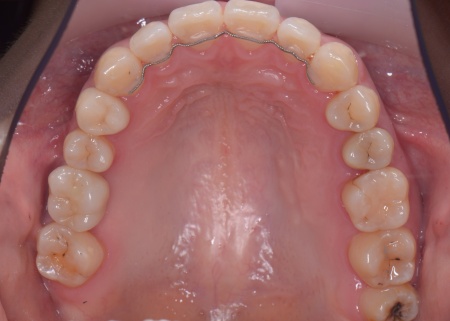

矯正治療では、歯に小さなボタンのような装置を取り付け、そこにワイヤーを通して歯を動かすマルチブラケット装置を使用しています。

インプラント手術後は矯正治療の仕上げを行い、装置を外しています。

歯並びが後戻りしないよう保定装置を装着していただき、その後、インプラントの上部に人工の歯を取り付けました。